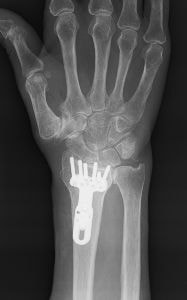

橈骨遠位端関節内粉砕骨折の術前(上)と術後(下)

橈骨遠位端骨折は、通年ですべての年齢層において最も多い上肢の骨折の一つです。骨折の主な原因は、転倒や高所から転落して手をつくことですが、手を強く捻って受傷することもあります。本骨折は、ケガの仕方、外力の大きさや骨の強さにより折れる場所や折れ方に様々なタイプ(型)があるのが特徴であり、尺骨や手根骨の骨折、手関節の靭帯損傷や神経障害を合併することもあります。

治療法は、骨折の型、骨折の徒手整復の可否、そして合併症の有無により異なり、比較的軽いものには保存的治療が、変形が大きかったり粉砕していたり骨折が関節内に及ぶ重症例には手術が行われてきました。しかしながら、近年は一人暮らしのご高齢の方の増加により、さほど重症でない骨折に対しても、早期から手の使用を可能とし、後遺障害を少なくするために手術を行うことが多くなってきています。

手術には、経皮的に鋼線を刺入して固定するピンニングや骨折部を直視下に整復してプレート固定する観血的手術があります。術後には早期の機能回復を目的としてリハビリ(作業療法)を行うことがあります。

橈骨遠位端変形治癒骨折の術前(左)と術後(右)